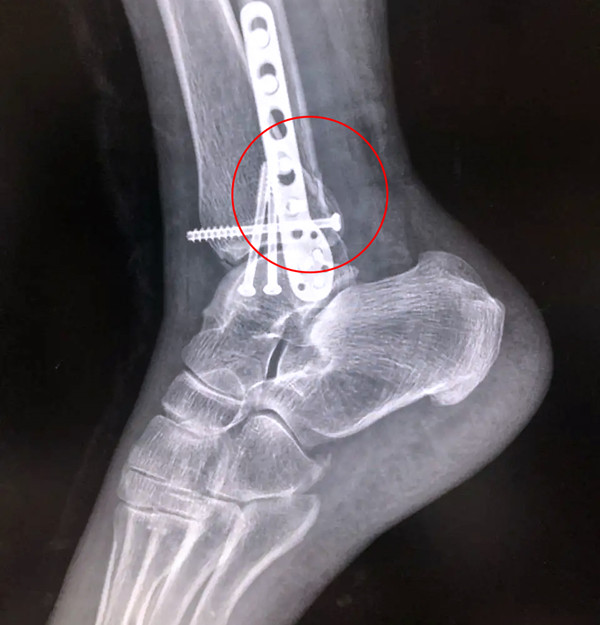

【醫療科普】Pilon骨折

有一種特殊類型的踝關節骨折,可能在X影像平片上就不能顯示出來,它就是脛骨的關節面往里塌陷,我們又稱之為叫“Pilon骨折”。當它往里塌陷后,我們在X影像平片上可能看不出來它是否塌陷,但是我們在CT上可以360°看到踝關節的影像,這樣就可以看出患者是否存在踝關節塌陷的骨折。同樣道理,我們在做Pilon骨折手術的時候,普通二維的X影像并不能判斷我們手術復位情況的好壞,這個時候如果醫生手上有能夠照三維影像的工具,那么對于醫生的準確手術是非常有好處的。

三維影像 助力復雜手術準確治療